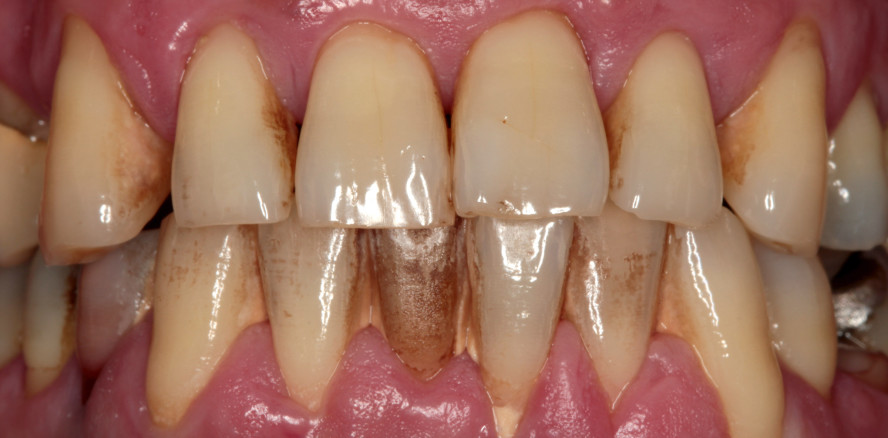

Der dicke gingivale Biotyp zeichnet sich durch eine breite Zahnform (großes Verhältnis von Kronenbreite zu Kronenlänge) und eine flache Girlandenform des Zahn­fleisches aus.1, 2 Die Zähne erscheinen rechteckig. Unabhängig von der Erfahrung des Behandlers lässt sich rein visuell dieser Biotyp zu ca. 70 Prozent richtig bestimmen.3 Eine höhere Sensitivität ist mit einer Parodontalsonde erreichbar. Beim dicken gingivalen Biotyp schimmert die Parodontalsonde beim Sondieren des Sulkus nicht durch.4 Ist dies der Fall, beträgt die Dicke des Zahnfleisches in der Regel 1 mm oder mehr.5 Je dicker die Gingiva ist und je viereckiger die Zähne sind, desto häufiger ist die Papille vollständig vorhanden.6 Die Prävalenz für den dicken gin­givalen Biotyp ist bei Männern im Vergleich zu Frauen erhöht.7, 8

Der dünne gingivale Biotyp zeichnet sich durch eine schmale Zahnform (kleines Verhältnis von Kronenbreite zu Kronenlänge) und ausgeprägte Girlandenform des Zahnfleisches aus.1, 2 Die Zähne erscheinen dreieckig. Nur zu 50 Prozent lässt sich der dünne Biotyp rein ­visuell richtig bestimmen.3 Mithilfe der Parodontalsonde lässt sich der Biotyp sehr gut ermitteln. Diese schimmert beim Sondieren des Sulkus durch und ist in der Regel dünner als 1 mm.4, 5 Die Papille ist beim dünnen Gingiva-­typ durch die dreieckige Zahnform seltener vollständig vorhanden.6 Die Prävalenz für den dünnen Biotyp ist bei Frauen im Vergleich zu Männern erhöht.7, 8